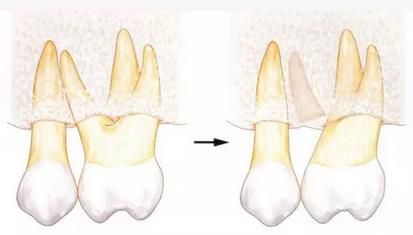

[針對牙根接近的牙周外科處理--牙體成形]

牙根一般根尖側(cè)較細(xì),所以牙根接近會使根尖部分減少。進行牙周外科處理時,如果能夠?qū)⒐墙M織切除一部分的話,就能通過骨組織切除和牙體成形來解決牙根接近的問題。

360截圖20170422101901128.jpg

▲圖6

如果可以在一定程度上削除骨組織的話,就可以通過牙體成形和骨外科處理來獲得biologic width,并可以解決牙根接近的問題。

以下為使用骨外科(骨組織切除)和牙體成形治療前牙牙根接近問題的病例。